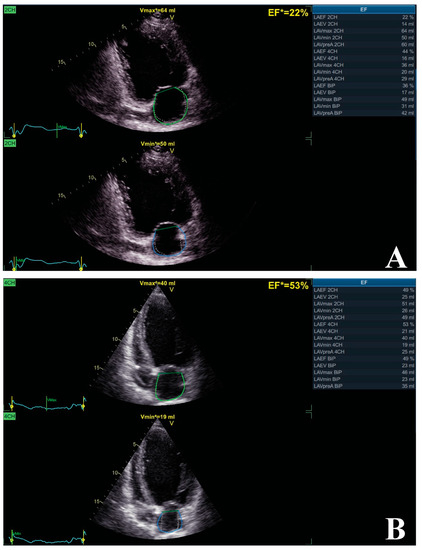

| Donal et al. | [83] | 2009 | 46 | LAPF LAVmax LAS-r | 6 Mo for the impact of CRT on LA remodeling | CRT significantly improved LAVmax, LAVmin, LAS-r, LAPF inducing LA reverse remodeling |

| Rossi et al. | [80] | 2013 | 52 | LAVmax LAVmin LAVpre-A | 6 Mo for the ability of LAVmax to predict CRT responsiveness | Lower LAVmax, LAVmin, and LAVpre-A were significantly associated with higher rate of CRT response |

| Kuperstein et al. | [76] | 2014 | 1785 | LAVmax | 6 Mo for all-cause mortality and HF | Higher LAVmax is associated with outcome Each 1% reduction in LAV = 4% reduction in hazard for HF/death |

| Lupu et al. | [82] | 2018 | 28 | LAVmax LAVmin LAVpre-A; LATF, LAPF, LAAF | 3 Mo for the impact of CRT on LA volumes and phasic functions | CRT has beneficial effects on LAVmax, LAVmin, and LAVpre-A, even within first days of implant |